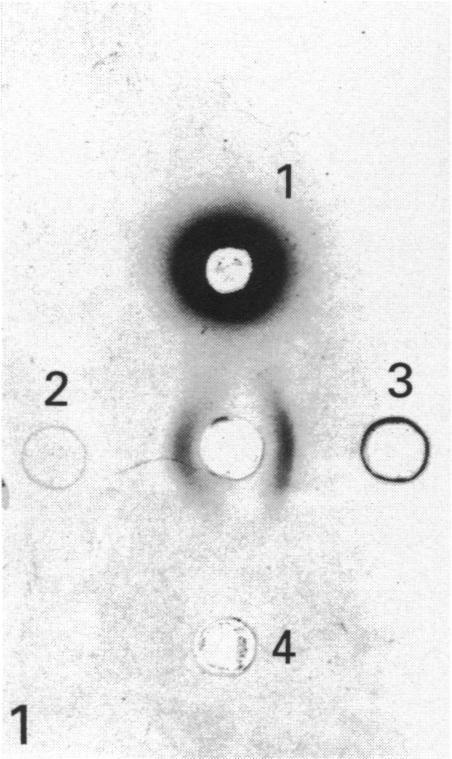

The localisation and ontogenic expression of heart fatty acid binding protein (H-FABP) were immunochemically examined in the entire body of the rat. In muscles, H-FABP immunoreactivity was observed not only in cardiac muscle cells but also in red skeletal muscles, where gold particles indicating the immunoreaction sites are distributed evenly in the sarcoplasm except for the interior of membranous organelles. In the urogenital system, the immunoreactivity was preferentially demonstrated in the distal tubular epithelial cells in the kidney, and in the superficial epithelial cells in the urinary bladder. The H-FABP immunoreactivity was further found in cells characterised by numerous lipid droplets, such as interstitial cells of the theca interna in the ovary and those of Leydig in the testis, and cell Element III in the placenta. In the digestive system, parietal cells in the stomach and pancreatic beta-cells were immunoreactive to H-FABP. In addition, capillary endothelial cells were immunostained in the cardiac and red skeletal muscles, the exocrine pancreas, digestive tract and thymus. From the rather wide distribution of H-FABP, it is suggested that H-FABP plays some fundamental roles in the active metabolism of fatty acids in the body. The present findings also indicate that H-FABP is a useful marker for the morphological study of interstitial cells in the ovary and testis and parietal cells in the stomach.

采用免疫化学方法对大鼠全身心脏脂肪酸结合蛋白(H-FABP)的定位及个体发生表达进行了研究。在肌肉中,不仅在心肌细胞中观察到H-FABP免疫反应性,在红色骨骼肌中也观察到了,除膜性细胞器内部外,表明免疫反应位点的金颗粒均匀分布于肌浆中。在泌尿生殖系统中,免疫反应性优先出现在肾脏远曲小管上皮细胞和膀胱表层上皮细胞中。在以大量脂滴为特征的细胞中也进一步发现了H-FABP免疫反应性,如卵巢内泡膜间质细胞、睾丸间质细胞以及胎盘的细胞成分III。在消化系统中,胃壁细胞和胰腺β细胞对H-FABP呈免疫反应性。此外,在心肌、红色骨骼肌、外分泌胰腺、消化道和胸腺的毛细血管内皮细胞也被免疫染色。鉴于H-FABP分布相当广泛,提示其在机体脂肪酸的活跃代谢中发挥着某些基本作用。本研究结果还表明,H-FABP是卵巢和睾丸间质细胞以及胃壁细胞形态学研究的有用标志物。